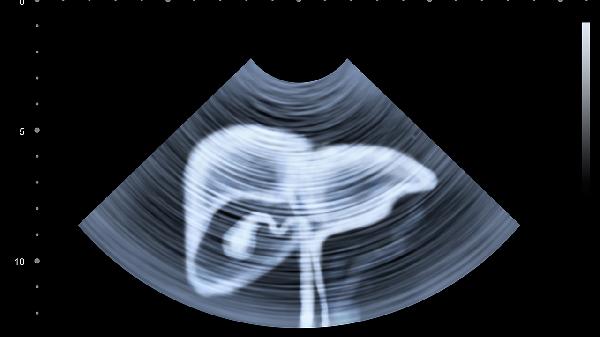

肝脏血管瘤通常生长缓慢且边界清晰,多数无症状,体积较大时可能出现压迫症状。影像学表现为均匀强化或周边结节样强化,甲胎蛋白水平正常。小肝癌生长较快且边界模糊,早期可能出现乏力、消瘦等症状,影像学表现为动脉期快速强化和静脉期快速消退,甲胎蛋白水平可能升高。

建议存在肝脏占位性病变的患者及时到肝胆外科就诊,通过增强CT或核磁共振明确诊断。日常生活中应避免饮酒和滥用药物,定期进行肝脏超声检查,发现异常及时干预。